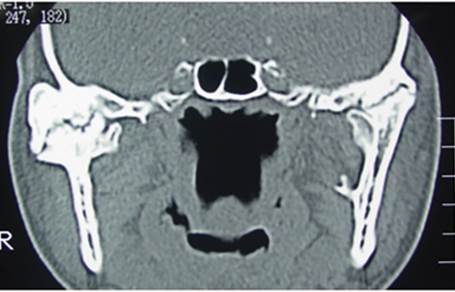

We asked him to get a preliminary CT scan to confirm our suspicion that showed a classical picture of fusion of the joint to the skull base.

In the CT scan image shown here, you can see a large boulder-like enlargement of the joint. This is the ankylotic mass.